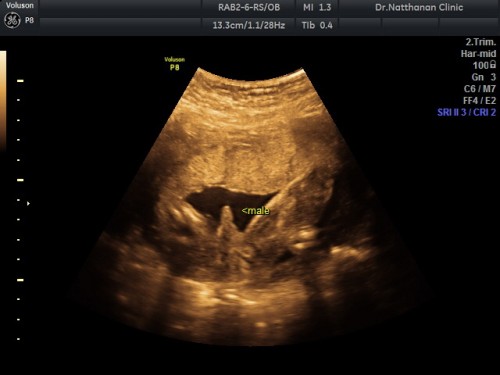

คุณแม่บ้านอื่นเตรียมของกันประมาณช่วงไหนคะ ตอนนี้ 22 w รู้เพศลูกแล้ว ว่าจะเตรียมของไว้เลย จะมีผลอะไรไหมคะ